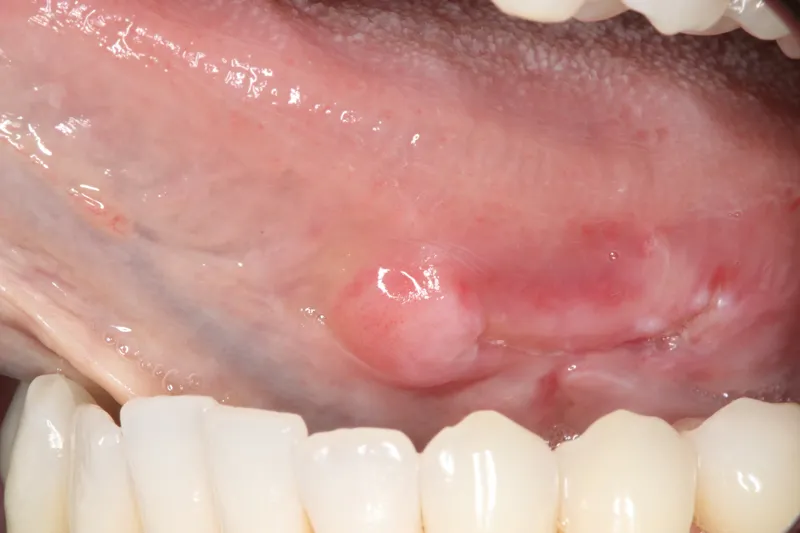

- Any lumps, bumps, rough or tender spots on your lips, gums or any other part of your mouth

- Red, white or spotted patches in or on the mouth